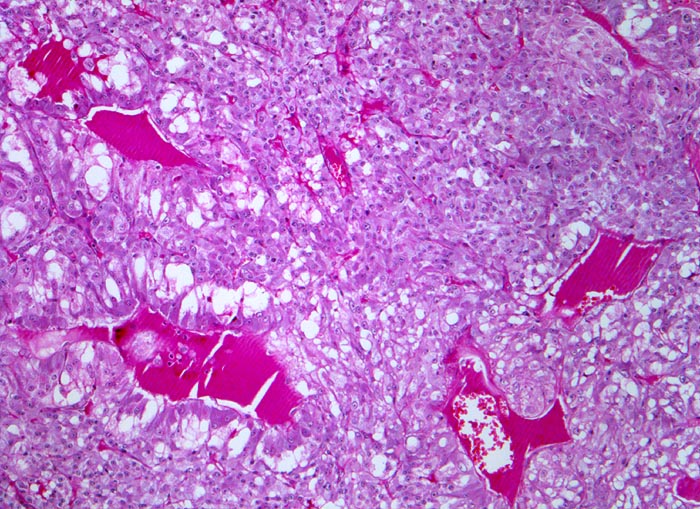

Phaeochromozytom

«Zellballen» aus teils spindelig konfigurierten, grossen Tumorzellen. In den Bindegewebssepten um die Zellballen lassen sich zahlreiche dilatierte Blutgefässe nachweisen.

Der Patient klagt über rezidivierende Kopfschmerzen seit zirka zwei Monaten. In letzter Zeit hat er Alcacyl genommen, jedoch ohne Erfolg. Die Computertomographie des Abdomens zeigt einen 5cm grossen Tumor im Bereich der rechten Nebenniere. Die Familienanamnese für multiple endokrine Neoplasien (MEN) ist bland.